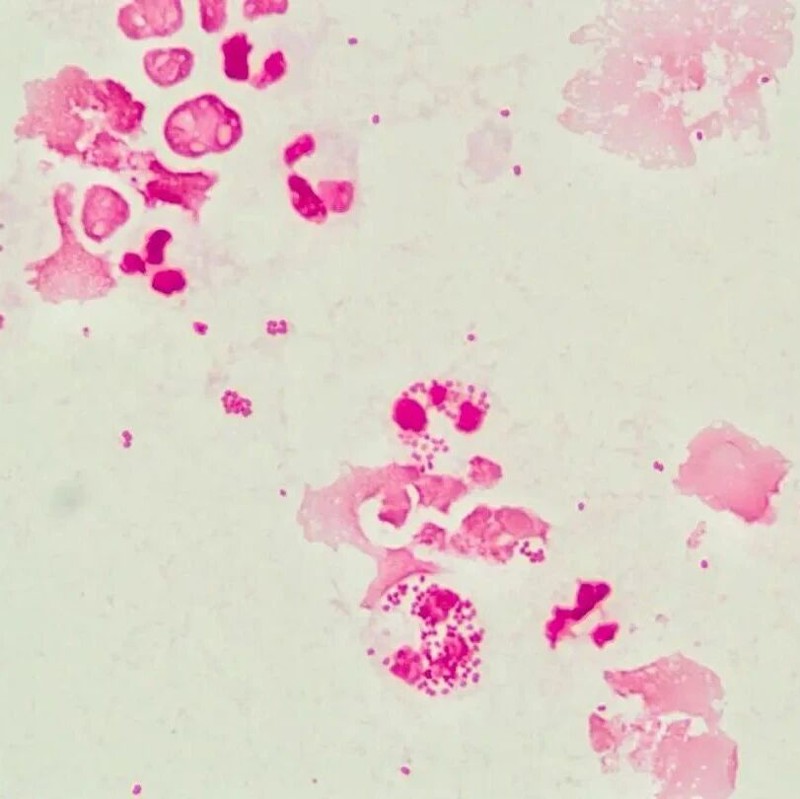

腹水细胞学三检纠偏,助诊潜伏间皮瘤:一例胸腹水细胞形态学在确诊恶性间皮瘤中的关键作用